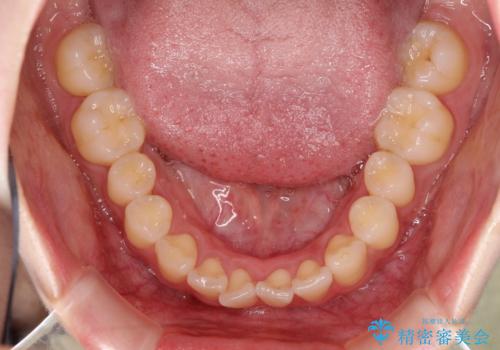

初診時の歯並びの状態としては、上下にガタガタがある状態であり、特に上の前歯(左上1番)の捻じれを最も気にしていらっしゃいました。

前歯の捻じれを改善するためにスペースを作る必要があり、前歯の歯の間を削って簡単に直す方法もありますが、奥歯のズレが認められたため、大臼歯後方のスペースを利用し、根本的な原因からしっかりと治療を行いました。